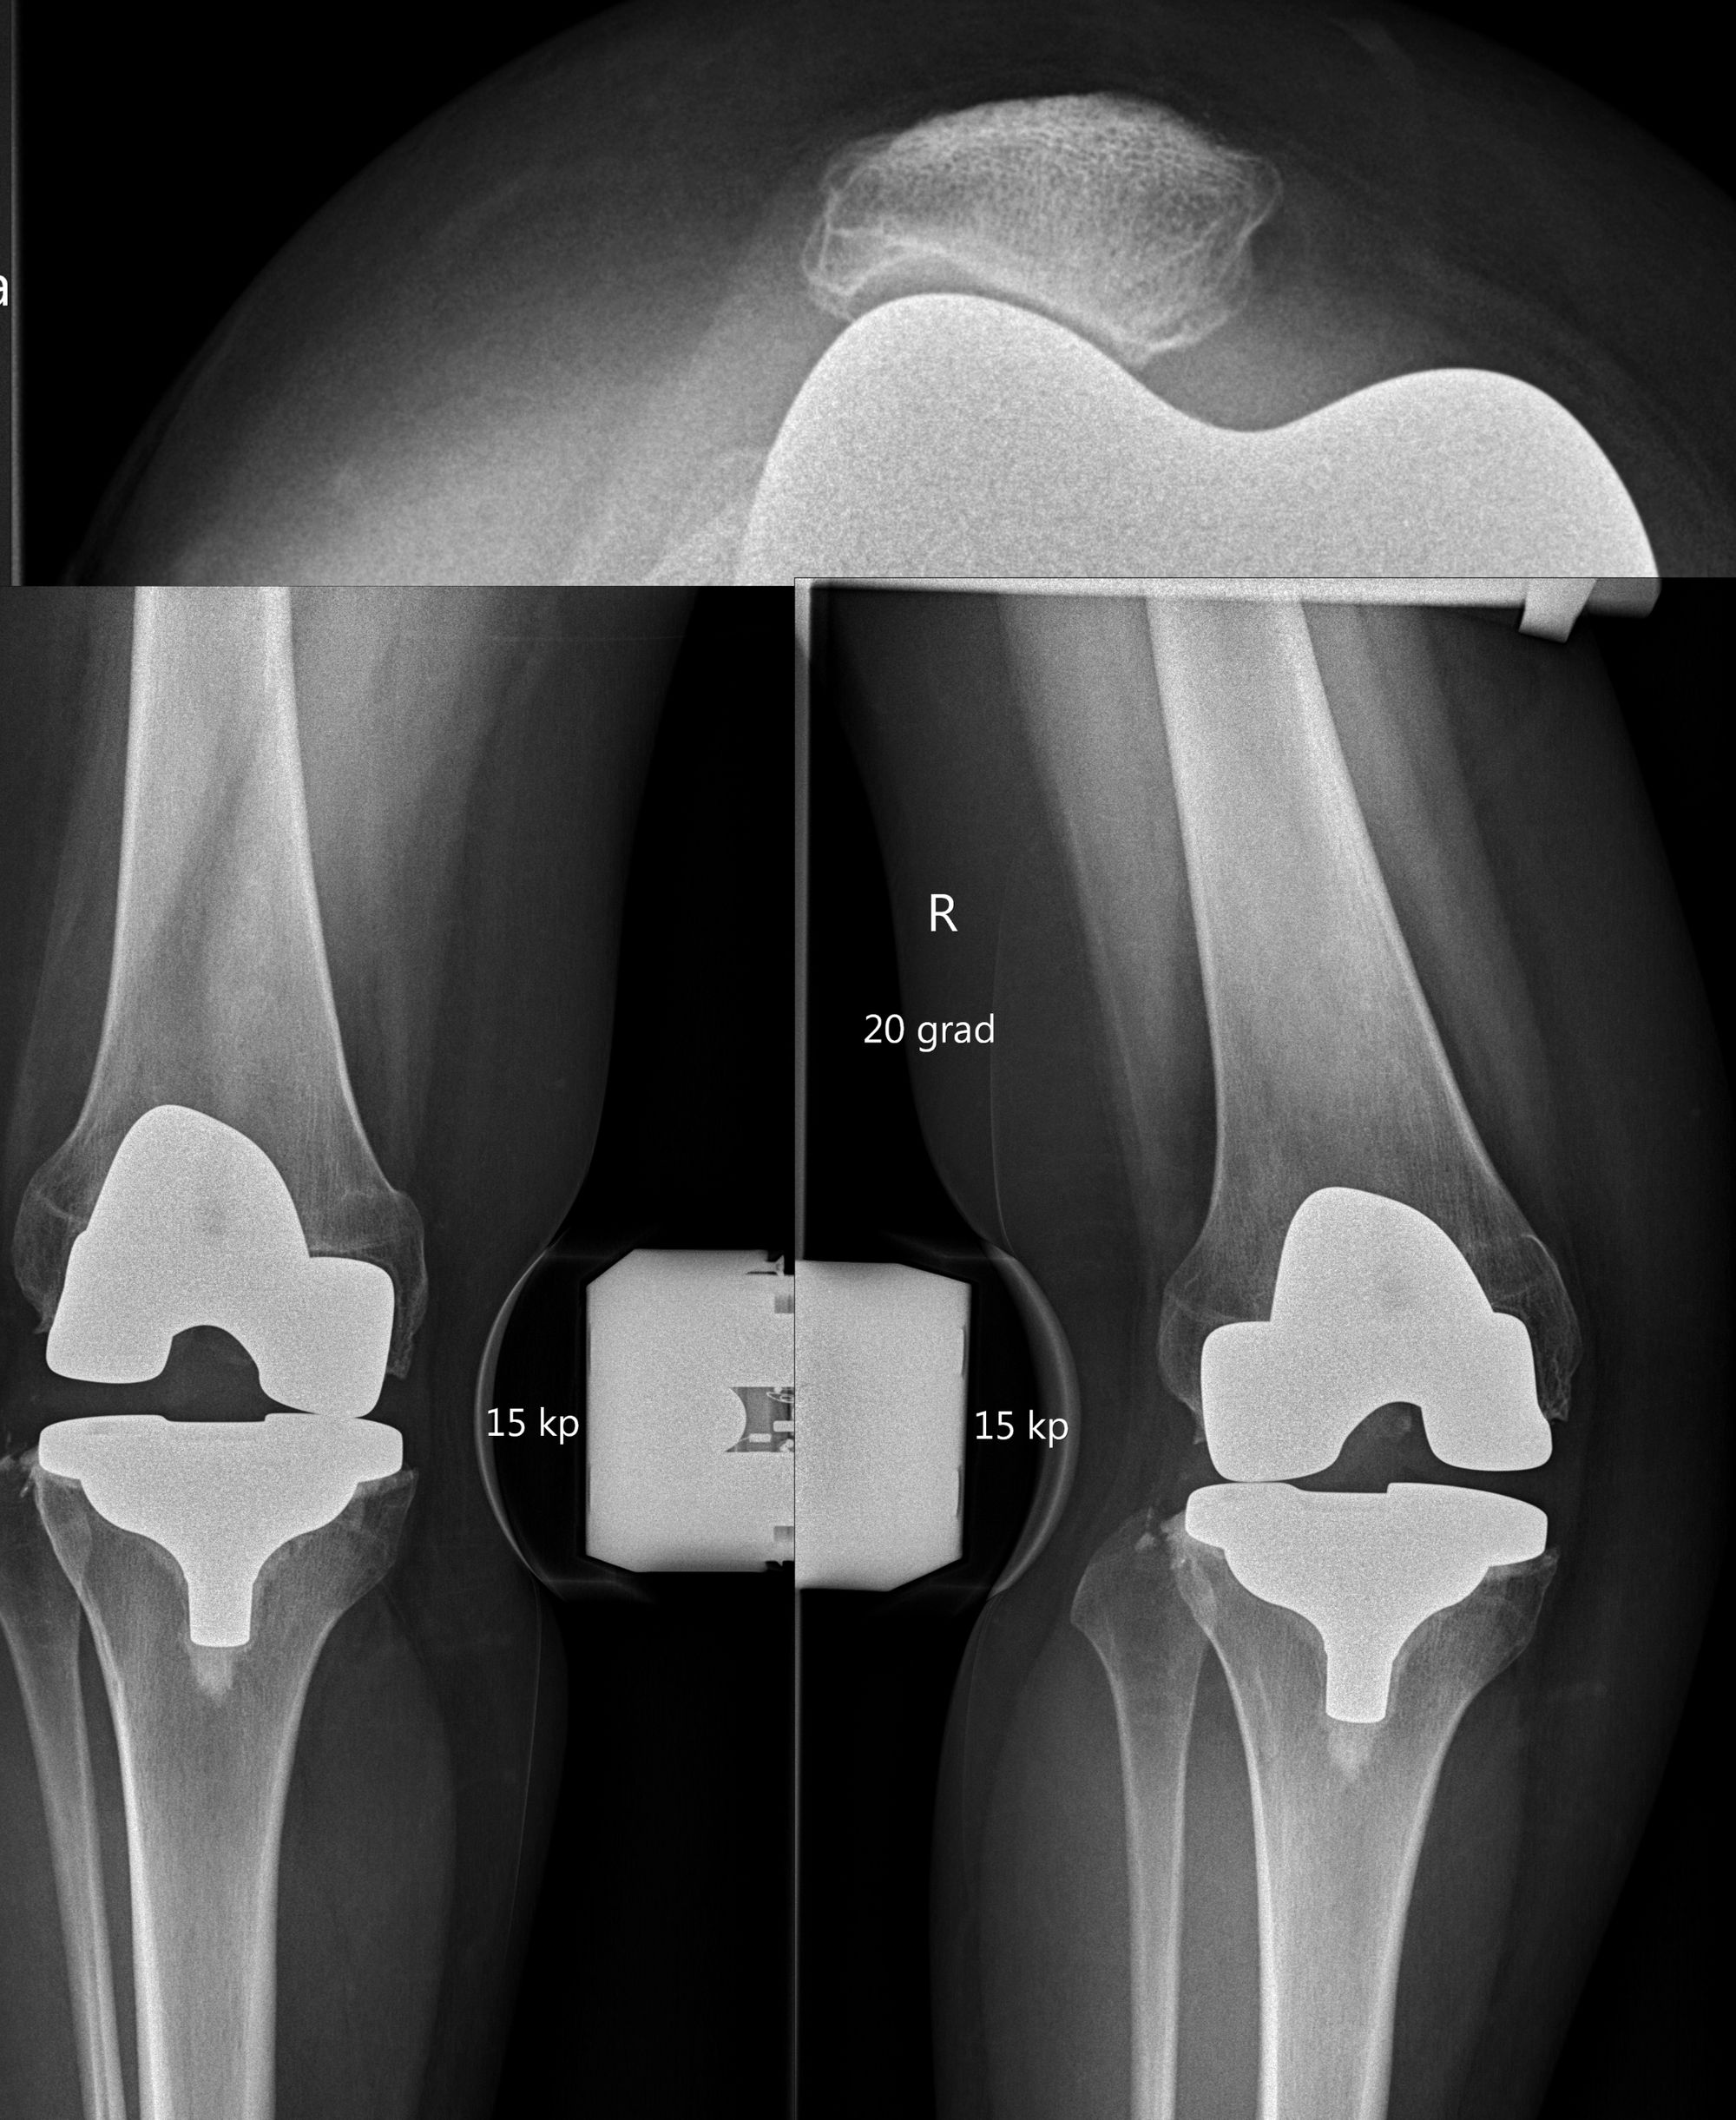

The surgical treatment depends on the causes identified using the diagnostic algorithm. There is no revision surgery for unclear pain. Only when the puzzle forms a nice picture and the diagnostic findings perfectly match with the patient’s symptoms, a revision surgery should be considered (Fig 5, 6).

In such a case it is highly important to meticulously discuss the patient`s expectations. Possible treatment options are the change of polyethylene inlay to a thinner or thicker one, a partial exchange of the prosthesis or a complete exchange of the prosthesis.

An isolated exchange of the inlay is however rarely indicated (e.g. poly wear) as often the knee is not well aligned or balanced. A partial exchange is indicated when loosening of only one TKA component is seen. The most common TKA revision is the complete exchange of both components. Generally, at least one higher constraint is used for revision TKA. Meaning a previous CR TKA is revised to a PS TKA. A PS TKA is revised for a semi-constrained (LCCK- limited condylar constraint) TKA and a LCCK is revised to a rotating or pure hinge TKA (Fig 7) .